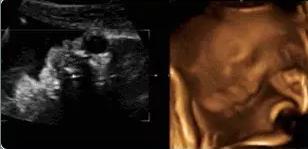

【在妇产科医院,你可以看到这样的胎宝】

本宝宝有些困了——打哈欠

麻麻,我正在挠耳朵

麻麻,我在咬手指哟!

霍霍,打拳啦~

本宝宝有些乏了——揉眼睛